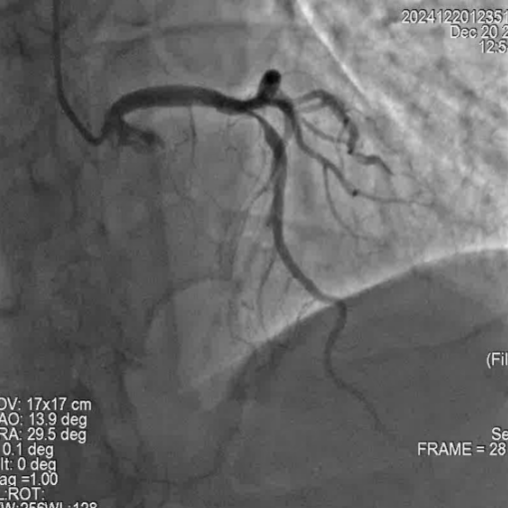

冠脉造影

手术过程